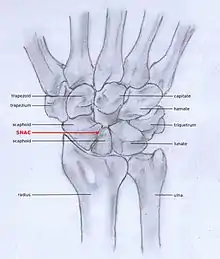

SNAC

Scaphoid fracture non-union changes the shape of the scaphoid bone and results in DISI malalignment.[2][5] Scaphoid Non-union Advanced collapse (SNAC) is the pattern of osteoarthritis that develops in relation to the malalignment.

In order to diagnose a SNAC wrist you need a PA view X-ray and a lateral view X-ray. As in SLAC, the lateral view X-ray is performed to see if there is a DISI.[12] Computed tomography (CT) or Magnetic Resonance Imaging (MRI) are rarely used to diagnose SNAC or SLAC wrist osteoarthritis because there is no additional value.[7] Also, these techniques are much more expensive than a standard X-ray. CT or MRI may be used if there is a strong suspicion for another underlying pathology or disease.[7]